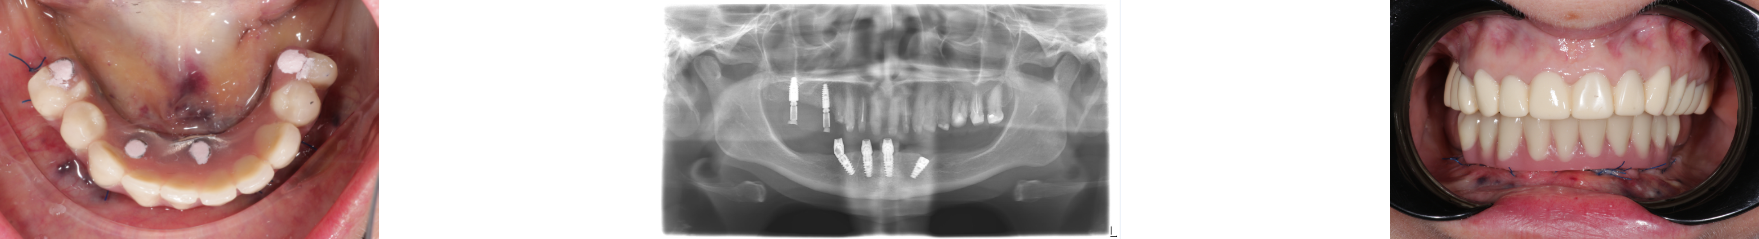

Пациент А

Пациент В

«Все на четырех».

Преимущества

технологии протезирования All-on-4( все на

четырех)

1. несъемный протез

фиксируется на 4х имплантатах;

2. подходит для

протезирования любой челюсти;

3. сроки лечения до 7

дней.

Резюмируя вышесказанное,

методика All-on-4 позволяет получить быстрый

результат протезирования, отказаться

от костной пластики и получить конструкцию

с высоким показателем стабильности.

В результате лечения

с применением методики All-on-4 пациент

получает восстановление функции жевания

и эстетики.